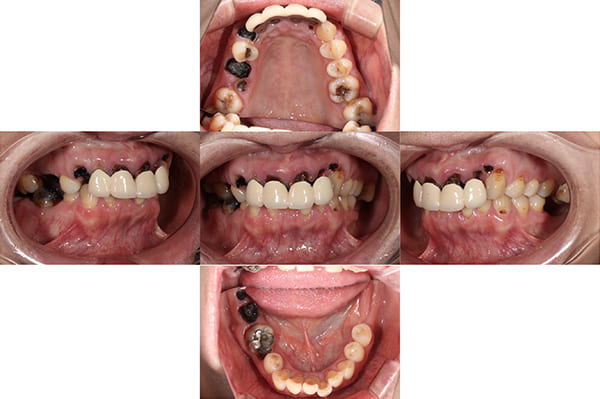

初診時の口腔内

「見た目を治したい」と来院された50代の女性の患者様です。

お口全体に虫歯がかなり進行しており、噛み合わせのバランスも崩れてる状態でした。

こちらが初診時の状態です